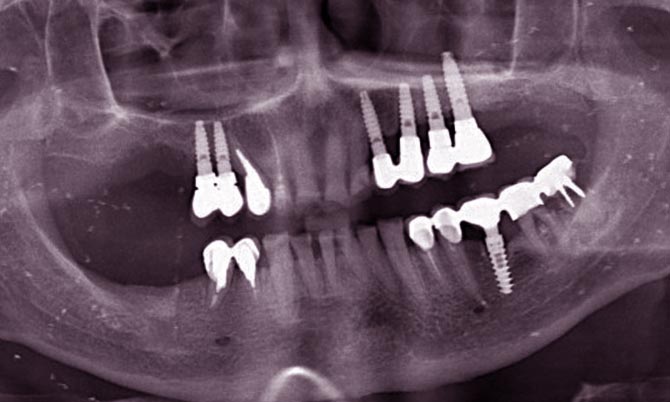

image Прежде, чем утверждать и проводить операцию имплантации, стоматолог должен провести диагностику пациента, которая включает осмотр полости рта, оценку состояния зубов и слизистой оболочки. Также во время диагностики врач должен сделать пациенту рентген костей лицевого скелета, чтобы исключить внутренние патологии строения, которые тоже относятся к абсолютным противопоказаниям. Не менее важным шагом перед имплантацией является консультация пациента с другими специалистами: терапевтом, аллергологом, неврологом, эндокринологом и другими врачами, по необходимости.

Противопоказаний к имплантации много, но хирург решает, возможна ли имплантация, с каждым пациентом индивидуально. Перед операцией пациент проходит полное медицинское обследование:

• анализ полости рта;

• рентгенографию челюстного аппарата, панорамный снимок или 3D-диагностику;

• электрокардиографию;

• общий и/или биохимический анализы крови;

• консультации эндокринолога, терапевта, аллерголога, невропатолога.